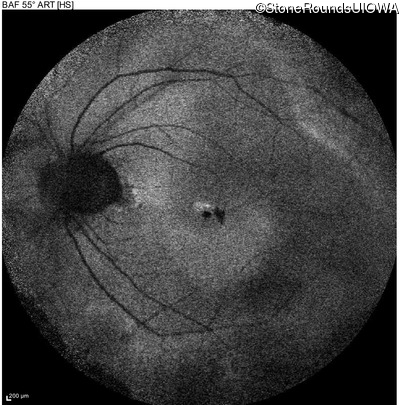

Blue Autofluorescence - Left - 20/40 +1

Exemplar